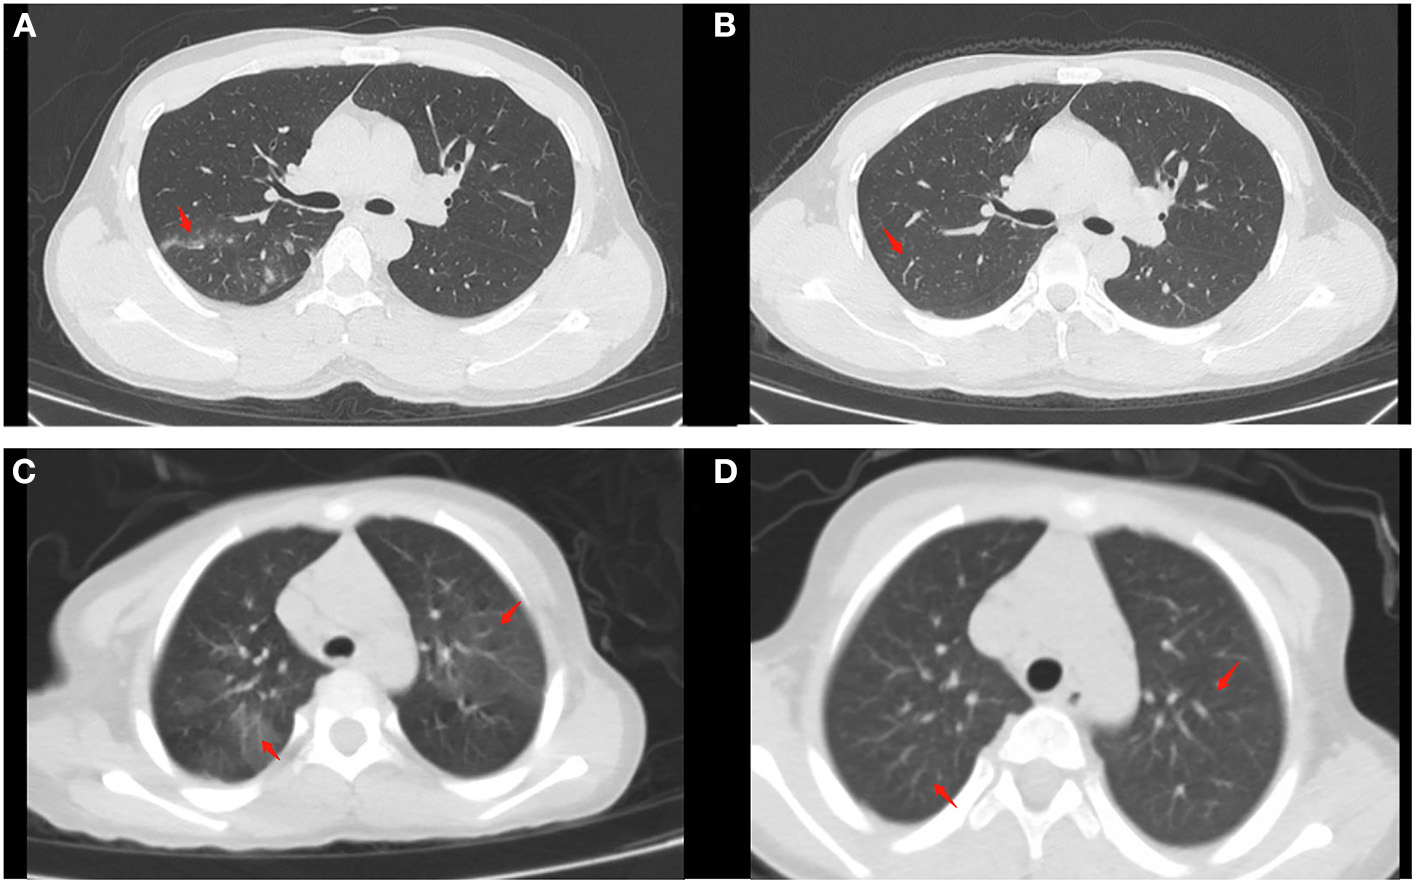

Additionally, the WBC count, NEU count, LYM count, and CRP level between the treatment-naïve and refractory groups before treatment were comparable (all P > 0.05). The LYM count and CRP level (P < 0.05) were significantly different between the treatment-naïve patients in the nasal irrigation group before and after treatment, while there were no statistical differences in the refractory patients before and after treatment (Table 7, Figure 3). The treatment-naïve and refractory patients showed significant improvement in inflammation, as shown by thoracic CT (Figures 4A–D).

Figure 4. Chest CT findings of moderate cases before and after treatment (as arrow points). (A) Patchy high-density shadow can be seen in the posterior segment of the upper lobe of the right lung before treatment in naïve patients. (B) The high-density shadow subsided after treatment in naïve patients. (C) Patchy high-density shadow and blurred edges can be seen in the upper lobes of both lungs in a refractory patient. (D) No significant abnormalities can be seen after treatment in the refractory patient.